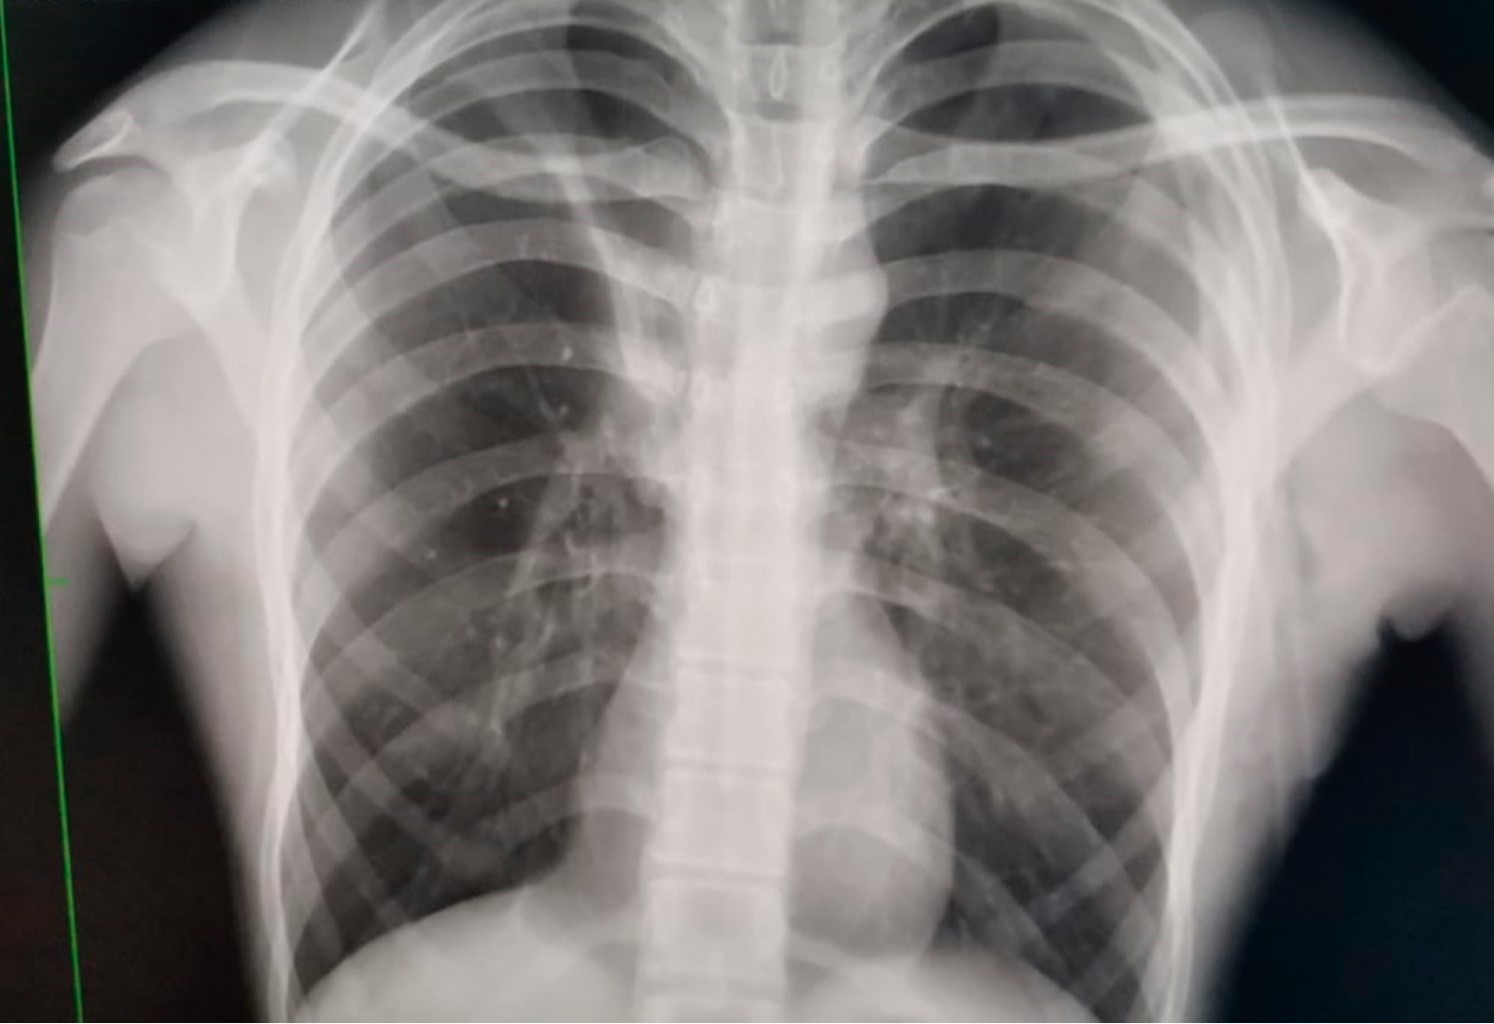

El tres semanas después acude al servicio de urgencias refiriendo dolor en hemitórax izquierdo de dos días de evolución, de inicio súbito, transflictivo, así como disnea en reposo, a la exploración física con hipoventilación de hemitórax izquierdo e hiperresonancia a la percusión, en la radiografía se observa neumotórax recidivante (Figura 1) y se coloca sonda endopleural, con adecuada expansión pulmonar (Figura 2) y buena evolución clínica, siete días después se realiza prueba con sonda pleural a sello, presentando disnea y dolor torácico, en radiografía de control se aprecia neumotórax izquierdo recidivante (Figura 3), por lo que se solicita tomografía computarizada observándose persistencia de neumotórax y bulla apical izquierda, por lo que se inicia protocolo quirúrgico para toracoscopia.

Figura 3